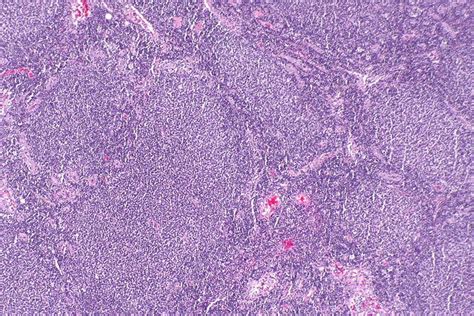

So, guys, let’s get real about follicular lymphoma . This isn’t just some random term; it’s a specific type of cancer that affects your lymphatic system. Think of your lymphatic system as a crucial part of your immune defense, a network of vessels and nodes that help your body fight off infections. Follicular lymphoma originates in B-cells, which are a type of white blood cell responsible for producing antibodies. These cancerous B-cells start multiplying uncontrollably, typically forming tumor clusters within the lymph nodes, but they can also appear in other parts of the body like the spleen, bone marrow, and even the digestive tract. The ‘follicular’ part of the name refers to the microscopic appearance of these cancerous cells; they tend to cluster in structures called germinal centers, which resemble follicles. What makes follicular lymphoma unique, and often a source of concern, is its generally slow-growing nature . This means that many people can live with it for years, sometimes without even knowing they have it. However, it’s still a cancer, and it can, in some cases, transform into a more aggressive form of lymphoma, like diffuse large B-cell lymphoma. The diagnosis usually involves a biopsy of an affected lymph node, where a pathologist examines the cells under a microscope and may perform various tests to confirm the diagnosis and determine the specific subtype. Staging is another critical step, which helps doctors understand how far the lymphoma has spread. This involves imaging tests and sometimes bone marrow biopsies. All this information is vital for treatment planning and, importantly for our discussion today, for assigning the correct ICD-10 codes. Understanding the biology of follicular lymphoma helps us appreciate why precise coding is so important for tracking its prevalence, treatment outcomes, and research efforts.